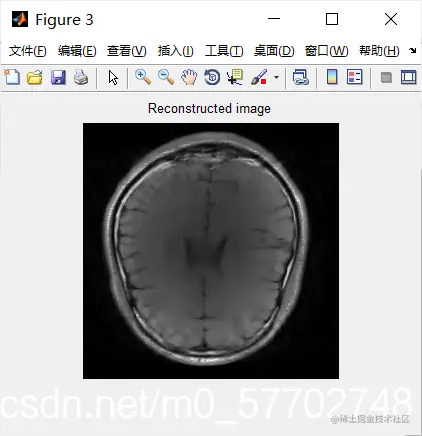

figure,imshow(abs(im1)); title('fully-sampled image') % fully sampled image.